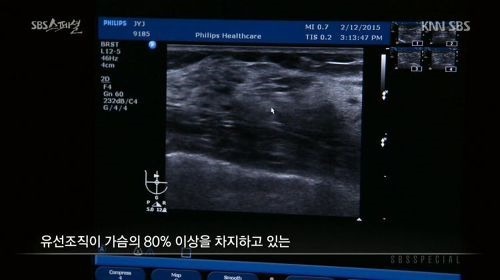

당시 방송에서 장윤주는 가슴을 초음파로 진단했습니다.

장윤주의 가슴 초음파 사진을 살펴본 의사는

"유선 조직이 가슴의 80%이상을 차지하고 있는 고도의 치밀유방이다. 지방 이식한 것도 안보인다. 보면 다 안다. (인공적인 것이)아무것도 없다. 자연산 맞다. 모유 잘 나오겠다"고 진단했습니다.

이에 장윤주는 "저의 가슴 수술논란을 확실히 풀었다"며 기뻐하며 "저도 꼭 모유수유하고 싶다"고 말했습니다.